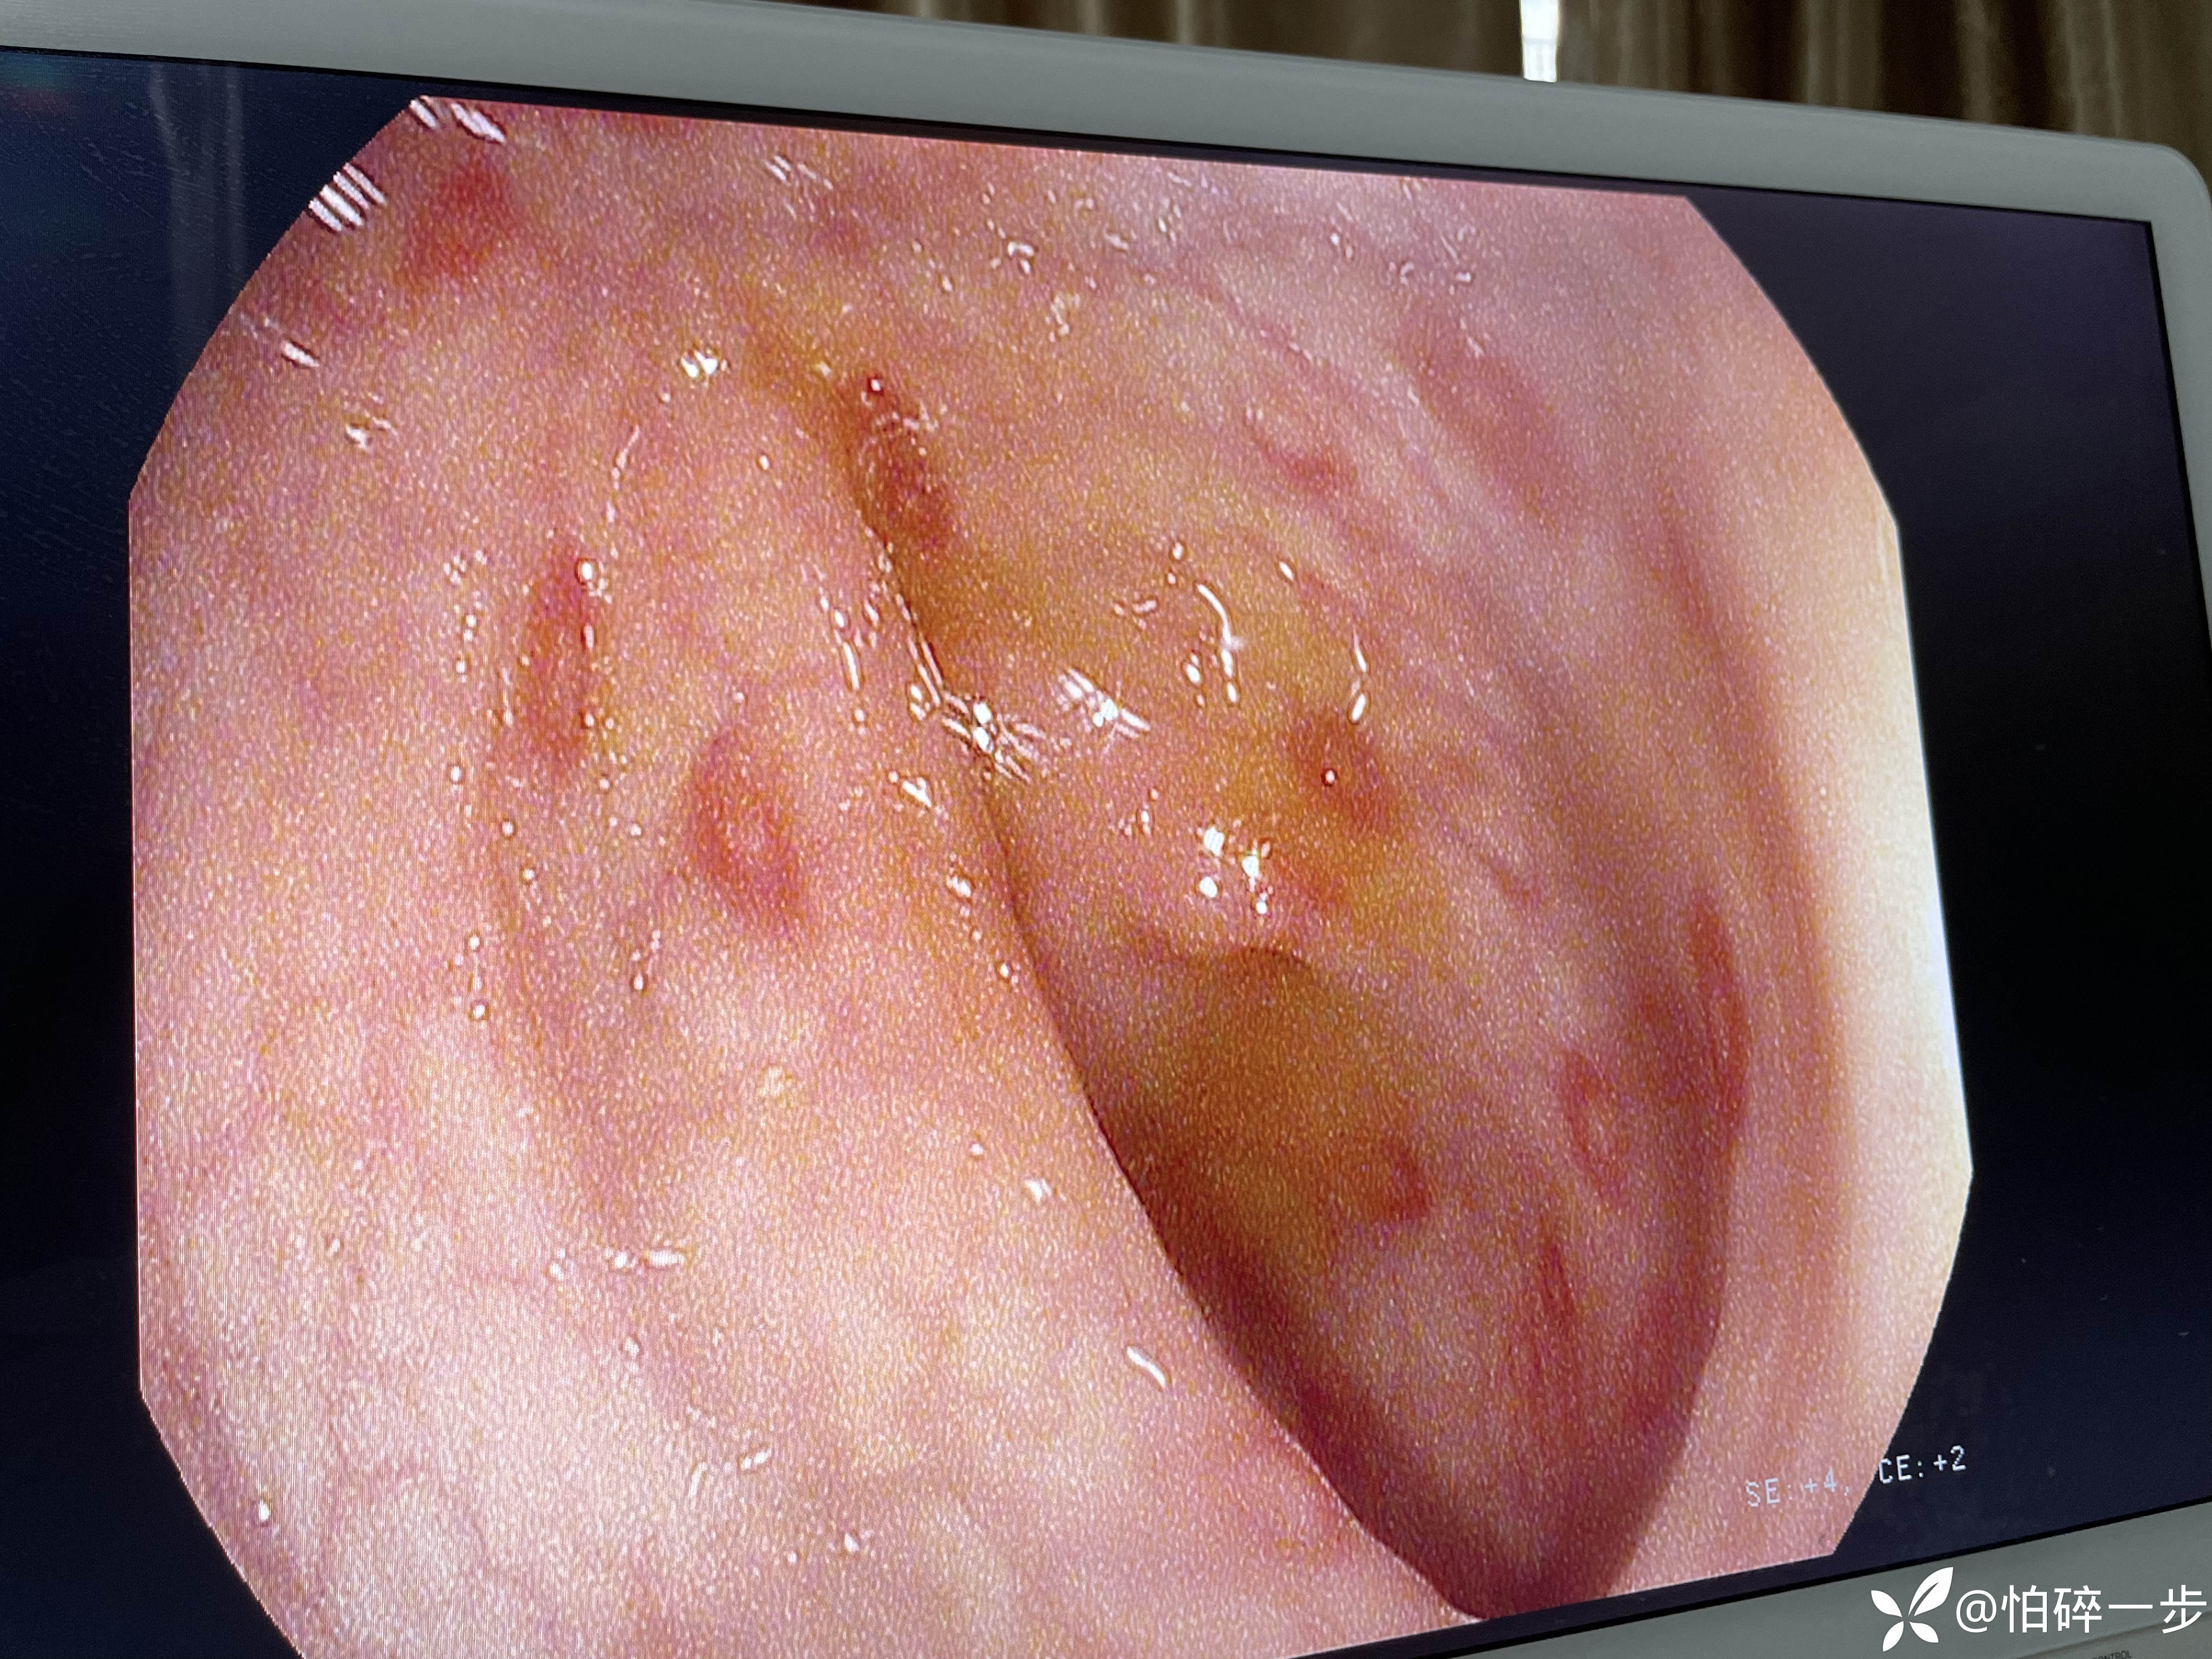

30岁,女性,2年前体检肠镜无异常。1月前无诱因突发脐周剧烈疼痛,之后出现大便改变,大便次数3-4次/天,大便变细。1周前再次出现左下腹剧烈疼痛,大便5-6次/天,大便不成形,排便结束时混有黏液,1周以来下腹部隐痛不适,有2次解黑便史,未进行治疗。本次门诊肠镜检查提示如下。请问各位站友意见如何?